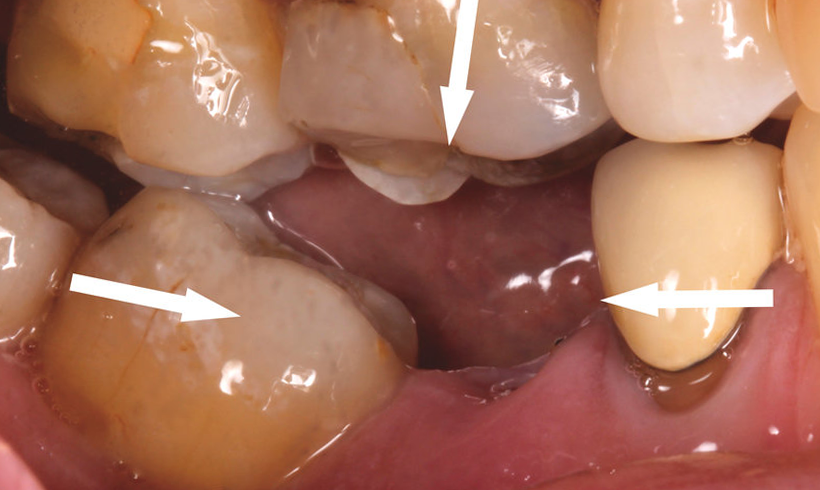

2. Xô Lệch Răng

– Các răng kế cận (răng số 4 và răng số 6) sẽ có xu hướng nghiêng về phía khoảng trống, gây xáo trộn khớp cắn. Điều này dẫn đến tình trạng khó nhai, đau khớp thái dương hàm và tăng nguy cơ sâu răng do thức ăn dễ bị mắc kẹt.